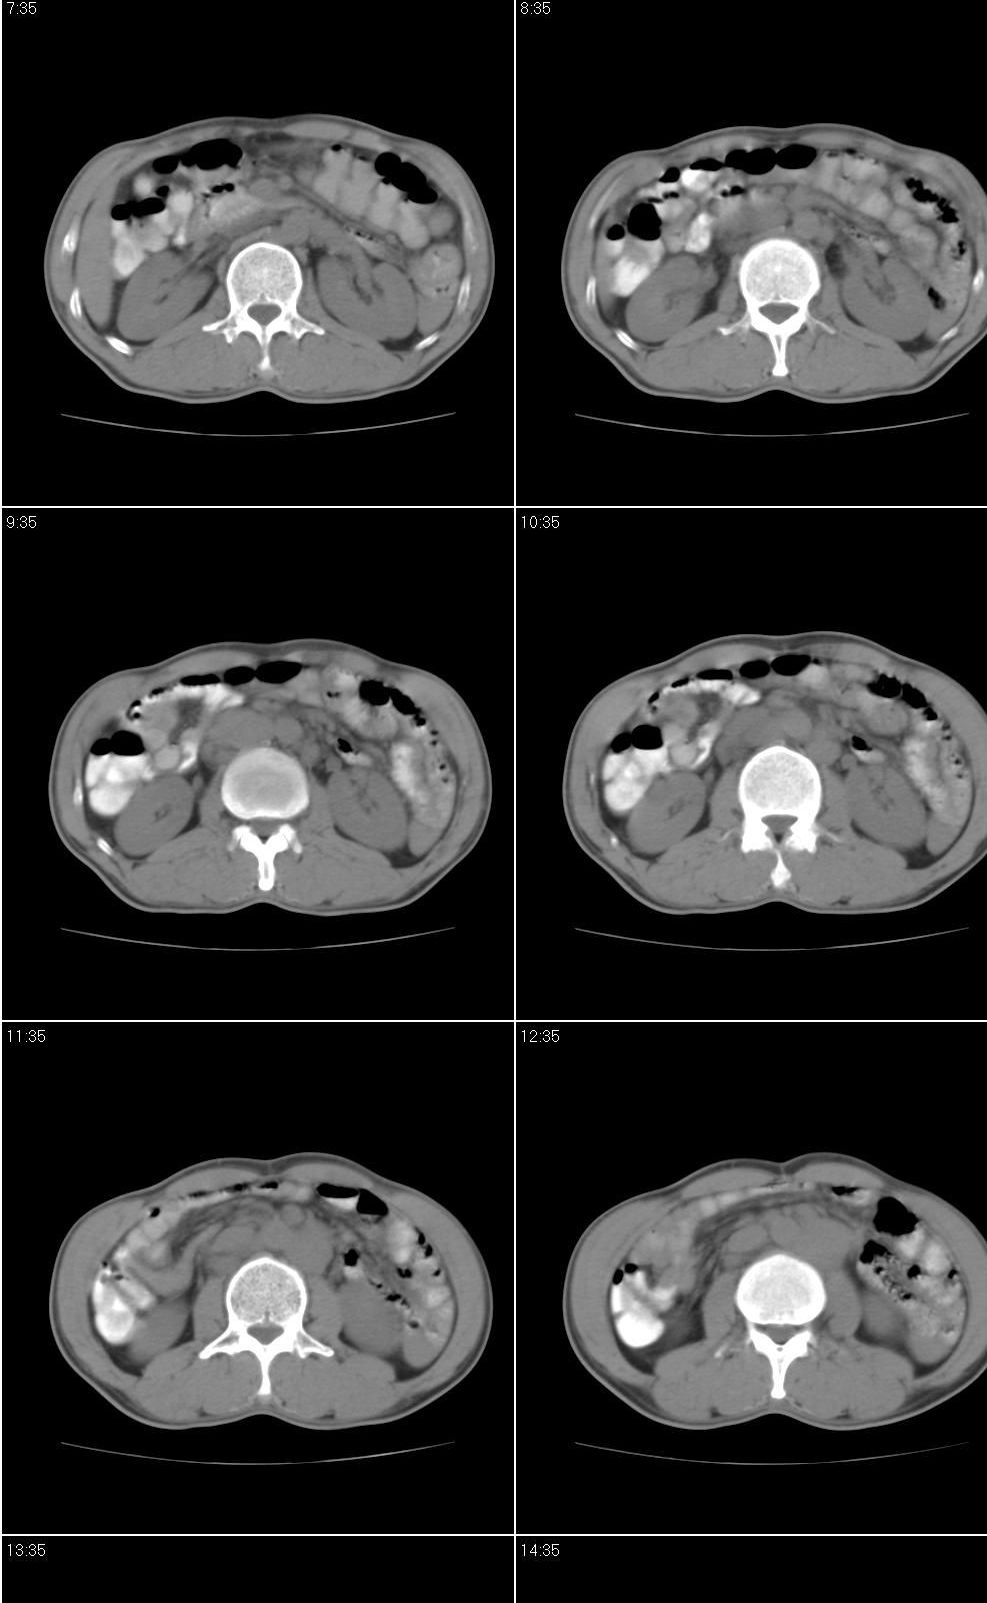

以下是引用jiangjing在2007-9-18 17:20:00的发言:[br]考虑生殖细胞肿瘤伴腹腔及腹膜后与腹股沟区淋巴转移,腹膜后大血管受压受侵

以下是引用老爱克斯新网客在2007-9-18 18:27:00的发言:[br]主动脉旁左侧腹股沟可见多发结节状病灶,1淋巴瘤,2转移瘤待除外,